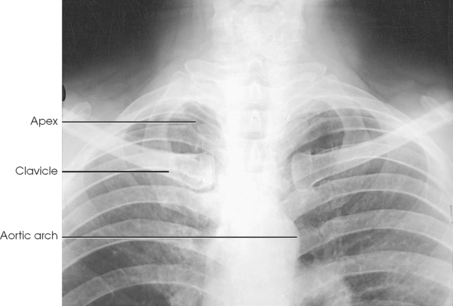

The lungs are the organs of respiration (Fig. 10-4). They are the mechanism for introducing oxygen into the blood and removing carbon dioxide from the blood. The lungs are composed of a light, spongy, highly elastic substance, the parenchyma, and they are covered by a layer of serous membrane. Each lung presents a rounded apex that reaches above the level of the clavicles into the root of the neck and a broad base that, resting on the obliquely placed diaphragm, reaches lower in back and at the sides than in front. The right lung is about 1 inch (2.5 cm) shorter than the left lung because of the large space occupied by the liver, and it is broader than the left lung because of the position of the heart. The lateral surface of each lung conforms with the shape of the chest wall. The inferior surface of the lung is concave, fitting over the diaphragm, and the lateral margins are thin. During respiration, the lungs move inferiorly for inspiration and superiorly for expiration (Fig. 10-5). During inspiration, the lateral margins descend into the deep recesses of the parietal pleura. In radiology, this recess is called the costophrenic angle (see Fig. 10-5, B). The mediastinal surface is concave with a depression, called the hilum, that accommodates the bronchi, pulmonary blood vessels, lymph vessels, and nerves. The inferior mediastinal surface of the left lung contains a concavity called the cardiac notch. This notch conforms to the shape of the heart.

Fig. 10-4 A, Three views of the lung. B, CT axial image through the thorax. Right and left lungs are shown in actual position within thorax and in relation to heart. Note nodule in right anterior lung (arrow). (B, Courtesy Siemens Medical Systems, Iselin, NJ.)